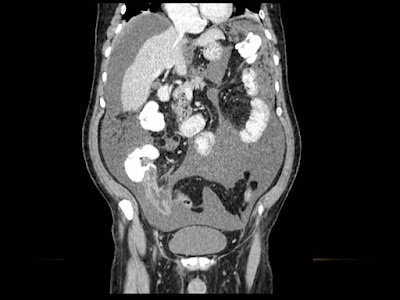

Paciente de 66 años con antecedente de pancreatitis, tomografía control.